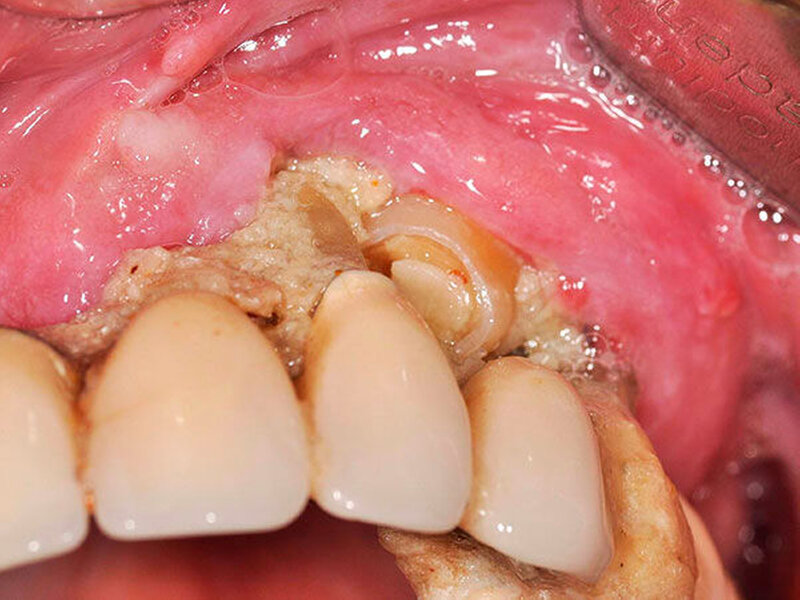

Bei Druckschmerzhaftigkeit im linken Oberkiefer und dort lokalisierter, stark gelockerter Brücke erfolgte die Überweisung des Patienten an die Abteilung für Mund-, Kiefer- und plastische Gesichtschirurgie der Universitätsmedizin Mainz. Klinisch stellte sich der Befund als druckschmerzhafte Strukturveränderung des Hartgewebes unterhalb der maxillär lokalisierten Brücke im rechten Oberkiefer bei drittgradig gelockerter Restbezahnung und insgesamt schlechter Mundhygiene dar (Abbildungen 1 und 2).

In der durchgeführten radiologischen Diagnostik zeigten sich ausgeprägte Parodontopathien mit Verdacht auf eine BRONJ bei gut begrenzter radiologischer Aufhellung mit Kieferhöhlenbeteilung (Abbildungen 3 bis 5). Unter der Verdachtsdiagnose einer BRONJ wurde somit die Indikation zur Zahnsanierung mit Exzision der pathologischen Veränderung im Oberkiefer gestellt. Nach Entfernung der gelockerten Brücke zusammen mit den die Brücke tragenden Zähnen zeigten sich große Mengen harten, anhaftenden Gewebes (Abbildung 6); der unter dem Befund liegende Knochen stellte sich klinisch als vital und ohne Anzeichen einer Nekrose dar.

Die feingewebliche mikroskopische Analyse wies eine fokale Ansammlung von Bakterien-Kolonien in fragmentiert vorliegendem Zelldetritus mit teilweise entzündlicher Überlagerung – im Sinne von Calculus dentis, also von Zahnstein – nach.